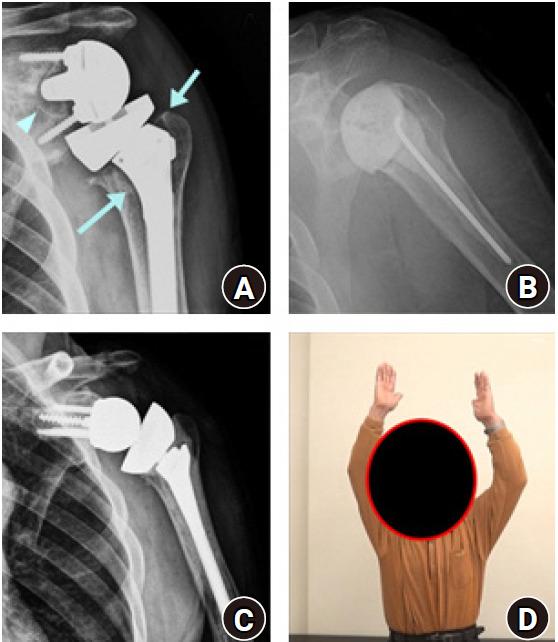

Reverse shoulder arthroplasty is an ideal treatment for glenohumeral dysfunction due to cuff tear arthropathy. As the number of patients treated with reverse shoulder arthroplasty is increasing, the incidence of complications after this procedure also is increasing. The rate of complications in reverse shoulder arthroplasty was reported to be 15%-24%. Recently, the following complications have been reported in order of frequency: periprosthetic infection, dislocation, periprosthetic fracture, neurologic injury, scapular notching, acromion or scapular spine fracture, and aseptic loosening of prosthesis. However, the overall complication rate has varied across studies because of different prosthesis used, improvement of implant and surgical skills, and different definitions of complications. Some authors included complications that affect the clinical outcomes of the surgery, while others reported minor complications that do not affect the clinical outcomes such as minor reversible neurologic deficit or minimal scapular notching. This review article summarizes the processes related to diagnosis and treatment of complications after reverse shoulder arthroplasty with the aim of helping clinicians reduce complications and perform appropriate procedures if/when complications occur.